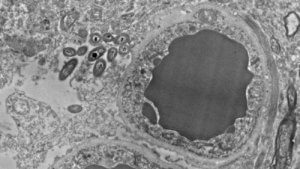

Uitgelichte afbeelding met dank aan Rosalinda Roberts, Courtney Walker, en Charlene Farmer.